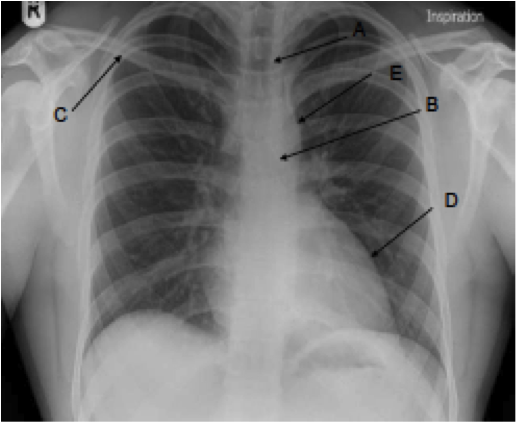

What can you see on this x-ray?

A) Trachea

B) Carina

C) Right Clavicle

D) Left Ventricle

E) Aortic knuckle